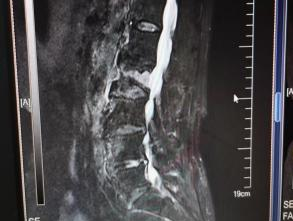

4月23日,贵州航天医院第58次晨读会由我院骨科副主任医师张艳金作学术交流,他以“加速康复指导下的快速手术”为题,详细讲解了老年股骨粗隆间骨折与儿童四肢骨折的临床诊疗难点,结合加速康复外科(ERAS)核心理念,重点阐述了ERAS理念在两大人群中的创新实践,实现患者入院后6至24小时内即可接受手术治疗。针对老年髋部骨折患者,提出通过多学科协作(MDT)与微创手术优化围术期管理,在确保安全前提下缩短术前等待时间,实施精准化麻醉及术后康复方案,可有效降低并发症发生率、改善患者生活质量和预后效果。在儿童骨折领域,强调微创术式与心理干预并行的双轨策略,既减少手术创伤对骨骼发育的影响,同时关注患儿心理疏导,实现生理功能与心理健康同步康复。并通过典型案例的影像学资料与随访数据,直观展示了ERAS理念指导下骨科治疗模式的创新成果。 贵州航天医院骨科 专家简介 赵学平 中共党员,骨科党支部书记、主任,主任医师 临床擅长:从事骨科临床工作30余年,对骨科常见疾病的诊治具有丰富的临床经验。 世界中医药联合会脊柱康复专业委员会常务理事,中华中医药学会整脊分会常务委员,中国中西医结合学会骨伤科分会肢体矫形功能重建与康复专家委员会常务委员,中国研究性医院学会骨科创新与转换专业委员会关节外科学组保髋工作委员会常委,中国康复技术转化及发展促进会骨外科与康复技术转化专业委员会常务委员,泛珠三角区域运动医学联盟(PPRD-SMA)理事会常务理事,中国研究型医院学会运动医学专业委员会委员,贵州省中医药学会整脊分会副主任委员,贵州省中西医结合学会银质针专业委员会副主任委员,贵州省康复医学会骨与关节专业委员会常务委员,贵州省人民医院骨科专科联盟常务理事,贵州省康复医学会骨内科专业委员会常务委员,中华医学会贵州省骨科学会委员,贵州省康复医学会脊柱脊髓专业委员会常务委员,贵州省运动医学分会委员,贵州省康复医学会骨与软组织肿瘤专业委员会委员,遵义市医学会创伤分会副主任委员,贵州省康复医学会骨内科专业委员会遵义地区分会常务委员,遵义市医疗事故鉴定、伤残鉴定、工伤鉴定、司法鉴定专家。 长期从事骨科临床研究及教学工作,在国家级、省部级杂志发表论文20余篇,SCI论文2篇,参与主编骨科专著2部,主持省部级科研项目2项,参与指导省部级、市级科研项目6项。 陈明勇 骨科副主任,副主任医师 临床擅长:从事创伤骨科工作约20年,对骨缺损、骨不连、骨肿瘤、肢体畸形等的肢体矫形重建及功能重建,慢性化脓性骨髓炎的根治治疗、糖尿病足的保肢治疗、快速康复理念(ERAS)下的老年骨折的诊治,四肢复杂骨折的诊治,四肢骨折等微创手术治疗具有丰富的临床经验。 2004年毕业于遵义医学院临床专业,曾在中国人民解放军总医院、广西医科大学第一附属医院、上海第六人民医院骨科进修。中国中西医结合学会骨伤科专业委员会横向骨搬移治疗糖尿病足及微血管网再生学组首届委员,遵义市医学会创伤分会常务委员。 瞿 辉 中共党员,骨科副主任医师 临床擅长:对骨科的常见病、关节外科、脊柱外科及运动医学疾病的诊治具有丰富的临床经验,熟练掌握骨科手术操作技术。 毕业于遵义医学院临床医学系,2005年前往广州中山大学第一附院骨显微医学部进修学习,2011年前往成都华西医院进修学习,并多次在省内外学习骨科相关知识,是中华医学会骨科分会会员。 赵兴东 骨科主任医师 临床擅长:擅长骨科的常见病及各种创伤、四肢骨折创伤修复、骨感染、手足疾病的诊治和手足体表畸形的矫形整复,熟练掌握骨科四肢骨病及创伤的手术操作技术,尤其在四肢关节复杂性损伤、手足外伤、组织缺损创面、难治创面的皮瓣修复方面及平足、高弓足矫形方面及四肢慢性疼痛诊治、康复方面具有丰富的临床经验。 硕士研究生,毕业于遵义医学院临床外科系,2015年前往山东省立医院手足外科进修学习;遵义市医学分会创伤分会第一、二届委员,遵义市手外科医学会第二委届员会常务委员;在省级及省级以上期刊发表文章9篇,参编著作2部,参与主持并完成市级课题1项,参与市级课题2项、省级课题1项。 张艳金 中共党员,骨科副主任医师 临床擅长:从事骨外科工作16年,对复合伤、多发伤的救治、四肢骨干骨折、关节周围骨折、骨肿瘤、骨髓炎等诊治具有丰富的临床经验。 中共党员,硕士研究生,2006年本科毕业于山西医科大学第二临床医学院,2011年研究生毕业于北京军区总医院;在“老年COPD患者合并髋部骨折的诊治”国际合作课题组研究两年,在老年髋部骨折的诊治方面具有丰富的经验,并发表论文6篇;主持遵义市级课题1项,承担遵义医科大学的临床教学工作,获得遵义医科大学优秀带教老师荣誉。编撰有《骨科疾病诊疗精粹》一书,开展2项新技术,编撰地方规范《务川自治县创伤骨科常见疾病诊疗规范》一书。 张俊凯 骨科副主任医师 临床擅长:从事骨科临床工作28年,对创伤骨折、骨感染、骨缺损、骨不连等外科诊治,四肢骨折的微创手术治疗,四肢复杂骨折(如关节内粉碎性骨折、多发骨折等)的损伤控制及手术治疗等具有丰富的临床经验。 1995年毕业于遵义医学院临床专业,2009年前往复旦大学附属医院骨科进修1年。 卢懿明 中共党员,骨科副主任医师 临床擅长:从事骨科工作18年,对创伤骨折、四肢骨折的微创手术治疗、四肢复杂骨折(如关节内粉碎性骨折、多发骨折等)的损伤控制及手术治疗,尤其是髋部骨折的PFNA等微创技术,踝关节骨折、膝关节周围骨折的Mipo微创技术等具有丰富的临床经验,开展了4项新技术,发明6项新型专利技术。 2005年毕业于遵义医学院临床专业,2017年,前往南方医科大学第三附属医院骨科进修半年,回院后运用Mipo技术对骨干骨折及干骺端骨折的治疗技术,同时积极开展骨盆骨折、髋臼骨折腹直肌外侧切口的应用;发表了多篇专业论文,经常参与省内外学术交流会授课,获得医院荣誉称号多个。 邬夏荣 骨科副主任医师 临床擅长:从事骨科工作16年,对四肢复杂骨折、骨肿瘤的诊治,尤其是足踝创伤、慢性踝关节损伤、平足症等诊疗具有丰富的临床经验。 2006年毕业于遵义医科大学临床医学专业,曾在陆军军医大学西南医院进修学习,发表多篇骨科学术论文。 余德怀 中共党员,骨科副主任医师 临床擅长:从事骨科工作10余年,对运动医学、骨关节、脊柱外科常见病、多发病的诊治具有丰富的临床经验。 硕士研究生,2011年毕业于遵义医学院临床医学专业,曾前往遵义医科大学附属医院运动医学专业进修学习;是贵州省医学会运动医学分会青年委员,西部关节镜联盟委员;发表多篇骨科学术论文。 冯 乾 骨科副主任医师 临床擅长:从事骨科工作近20年,熟练掌握骨科多发病及常见病的诊治,尤其对脊柱退变性疾病的诊断及治疗具有丰富的临床经验,主要研究脊柱微创相关治疗方式,能熟练开展椎间孔镜及UBE。 曾前往北京大学第三医院进修学习疼痛及椎间孔镜、首都医科大学友谊医院专业进修脊柱内镜;是贵州省康复医学会第三届脊柱脊髓专业委员会委员;发明专利3项、发表脊柱外科专业论文多篇。 赵小锋 中共党员,骨科副主任医师 临床擅长:从事骨科临床工作11年,对骨科常见病、多发病诊疗有较为丰富的临床经验,擅长脊柱相关疾病诊断及治疗,尤其是颈、腰、腿疼痛疾病诊断及治疗,擅长胸腰椎骨折微创经皮穿刺内固定术、经皮穿刺椎体成形术、经皮穿刺脊柱内镜下腰椎间盘摘除术、单纯开创腰椎间盘摘除术、腰椎滑脱复位椎间植骨椎融合内固定术、腰椎管狭窄减压融合内固定术及人工髋、膝关节置换术等。 2012年毕业于遵义医学院外科学专业硕士研究生,2019年参加“遵义市115医学人才精英计划”于上海交通大学第一附属医院培训学习,2023年于北京大学第三人民医院脊柱外科进修学习,曾获得遵义市优秀医师荣誉称号。 遵义市手外科第一届委员,遵义市医学会创伤分会第一届委员,遵义市医学会创伤分会第二届委员,贵州省康复医学会第三届脊柱脊髓专业会委员,遵义市医学会烧伤与整形外科学分会委员,发表论文5篇,其中国家级核心期刊1篇,SCI论文1篇,主持市级课题1项并结题,参与市级课题2项。 贵州航天医院骨科 简介 基本情况 贵州航天医院骨科组建于20世纪60年代,前身是以创伤和断肢(断指)再植闻名于世的上海市第六人民医院骨科,中国断肢(断指)再植的奠基者、中科院院士陈仲伟等著名专家、学者多次莅临科室指导医疗、教学,是贵州省最早拥有专业骨科技术科室之一,在70年代开展了贵州省首例断肢(断指)再植手术。组建50余年来,诊治患者已逾百万,挽救了无数的伤病员,成为了保障遵义地区人民群众健康的重要支撑。 经过几代人的不懈努力,今天的骨科,已由创伤骨科发展至骨病、骨肿瘤、骨结核等领域,现有脊柱外科、关节外科、四肢创伤、手足外科四个亚专科,成为了集医疗、教学、科研于一体的综合学科,是贵州省临床重点专科、遵义市临床重点专科、遵义市骨科临床医学中心、遵义市基层骨科专科联盟理事长单位。 科室目前开放床位110张,共有医护人员50余人,副高级以上专家18人,硕士研究生15人。拥有一流骨科医疗设备多台,每年不定期选派优秀技术骨干到全国各大知名医学院校进修、学习、参观、交流,并邀请国内、国外知名专家教授来院进行交流、指导,通过不断引进国内外先进的诊疗技术,科室医疗技术水平稳步提升,为广大人民群众提供了优质的医疗服务。 专科特色 骨一科 (一)骨缺损、骨不连的肢体与功能重建 胫骨横向骨搬移技术治疗糖尿病足: (二)慢性骨髓炎的根治治疗 (三)肢体缺血性疾病如糖尿病足、脉管炎的保肢治疗 (四)皮瓣修复 (五)复杂创伤的治疗 (六)老年髋部骨折及小儿骨折快速手术 老年髋部骨折: 骨二科 (一)胸腰椎骨折微创经皮椎弓根螺钉固定术 (二)老年性骨质疏松性患者腰椎滑脱脊柱内固定术(骨水泥螺钉) (三)V形双通道脊柱内镜技术(VBE)腰椎融合术治疗腰椎退行性疾病 (四)老年性骨质疏松性骨折(PVP/PKP)术 (五)人工髋关节置换术 (六)双侧股骨头坏死人工全髋关节置换 (七)右侧全髋置换术后假体周围骨折翻修 (八)人工膝关节置换术 (九)人工膝关节假体松动翻修 (十)关节镜技术 传统手术切口 关节镜技术切口 诊疗范围 骨一科 1.四肢创伤、矫形。 2.手、足踝外科。 骨二科 end